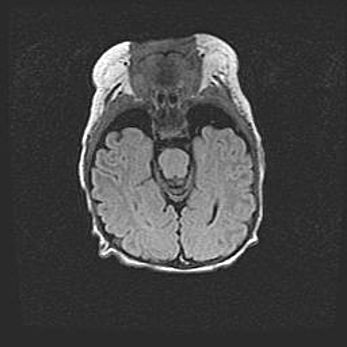

Неполная лизэнцефалия (пахигирия). Открытая гидроцефалия.

Возраст: 17 дней

Вес: 3110 г

Пол: мужской

Окружность головы: 33,5 см

Срок гестации: 35-36 недель

Лизэнцефалия—недоразвитие корковой пластинки и мозговых извилин в результате нарушения миграции нейронов коры. Поверхность мозговых полушарий гладкая. Микроскопически выявляется отсутствие нормальных слоев коры и скопление групп нейронов в подкорковом белом веществе.

Пахигирия—уменьшение числа вторичных извилин. В пораженном полушарии нервные клетки образуют толстый недифференцированный слой с неправильно расположенными нервными волокнами и группами гетеротопных клеток. Нервные клетки незрелые. Белое вещество истончено. При этом нередко аномально развит корково-спинномозговой путь.